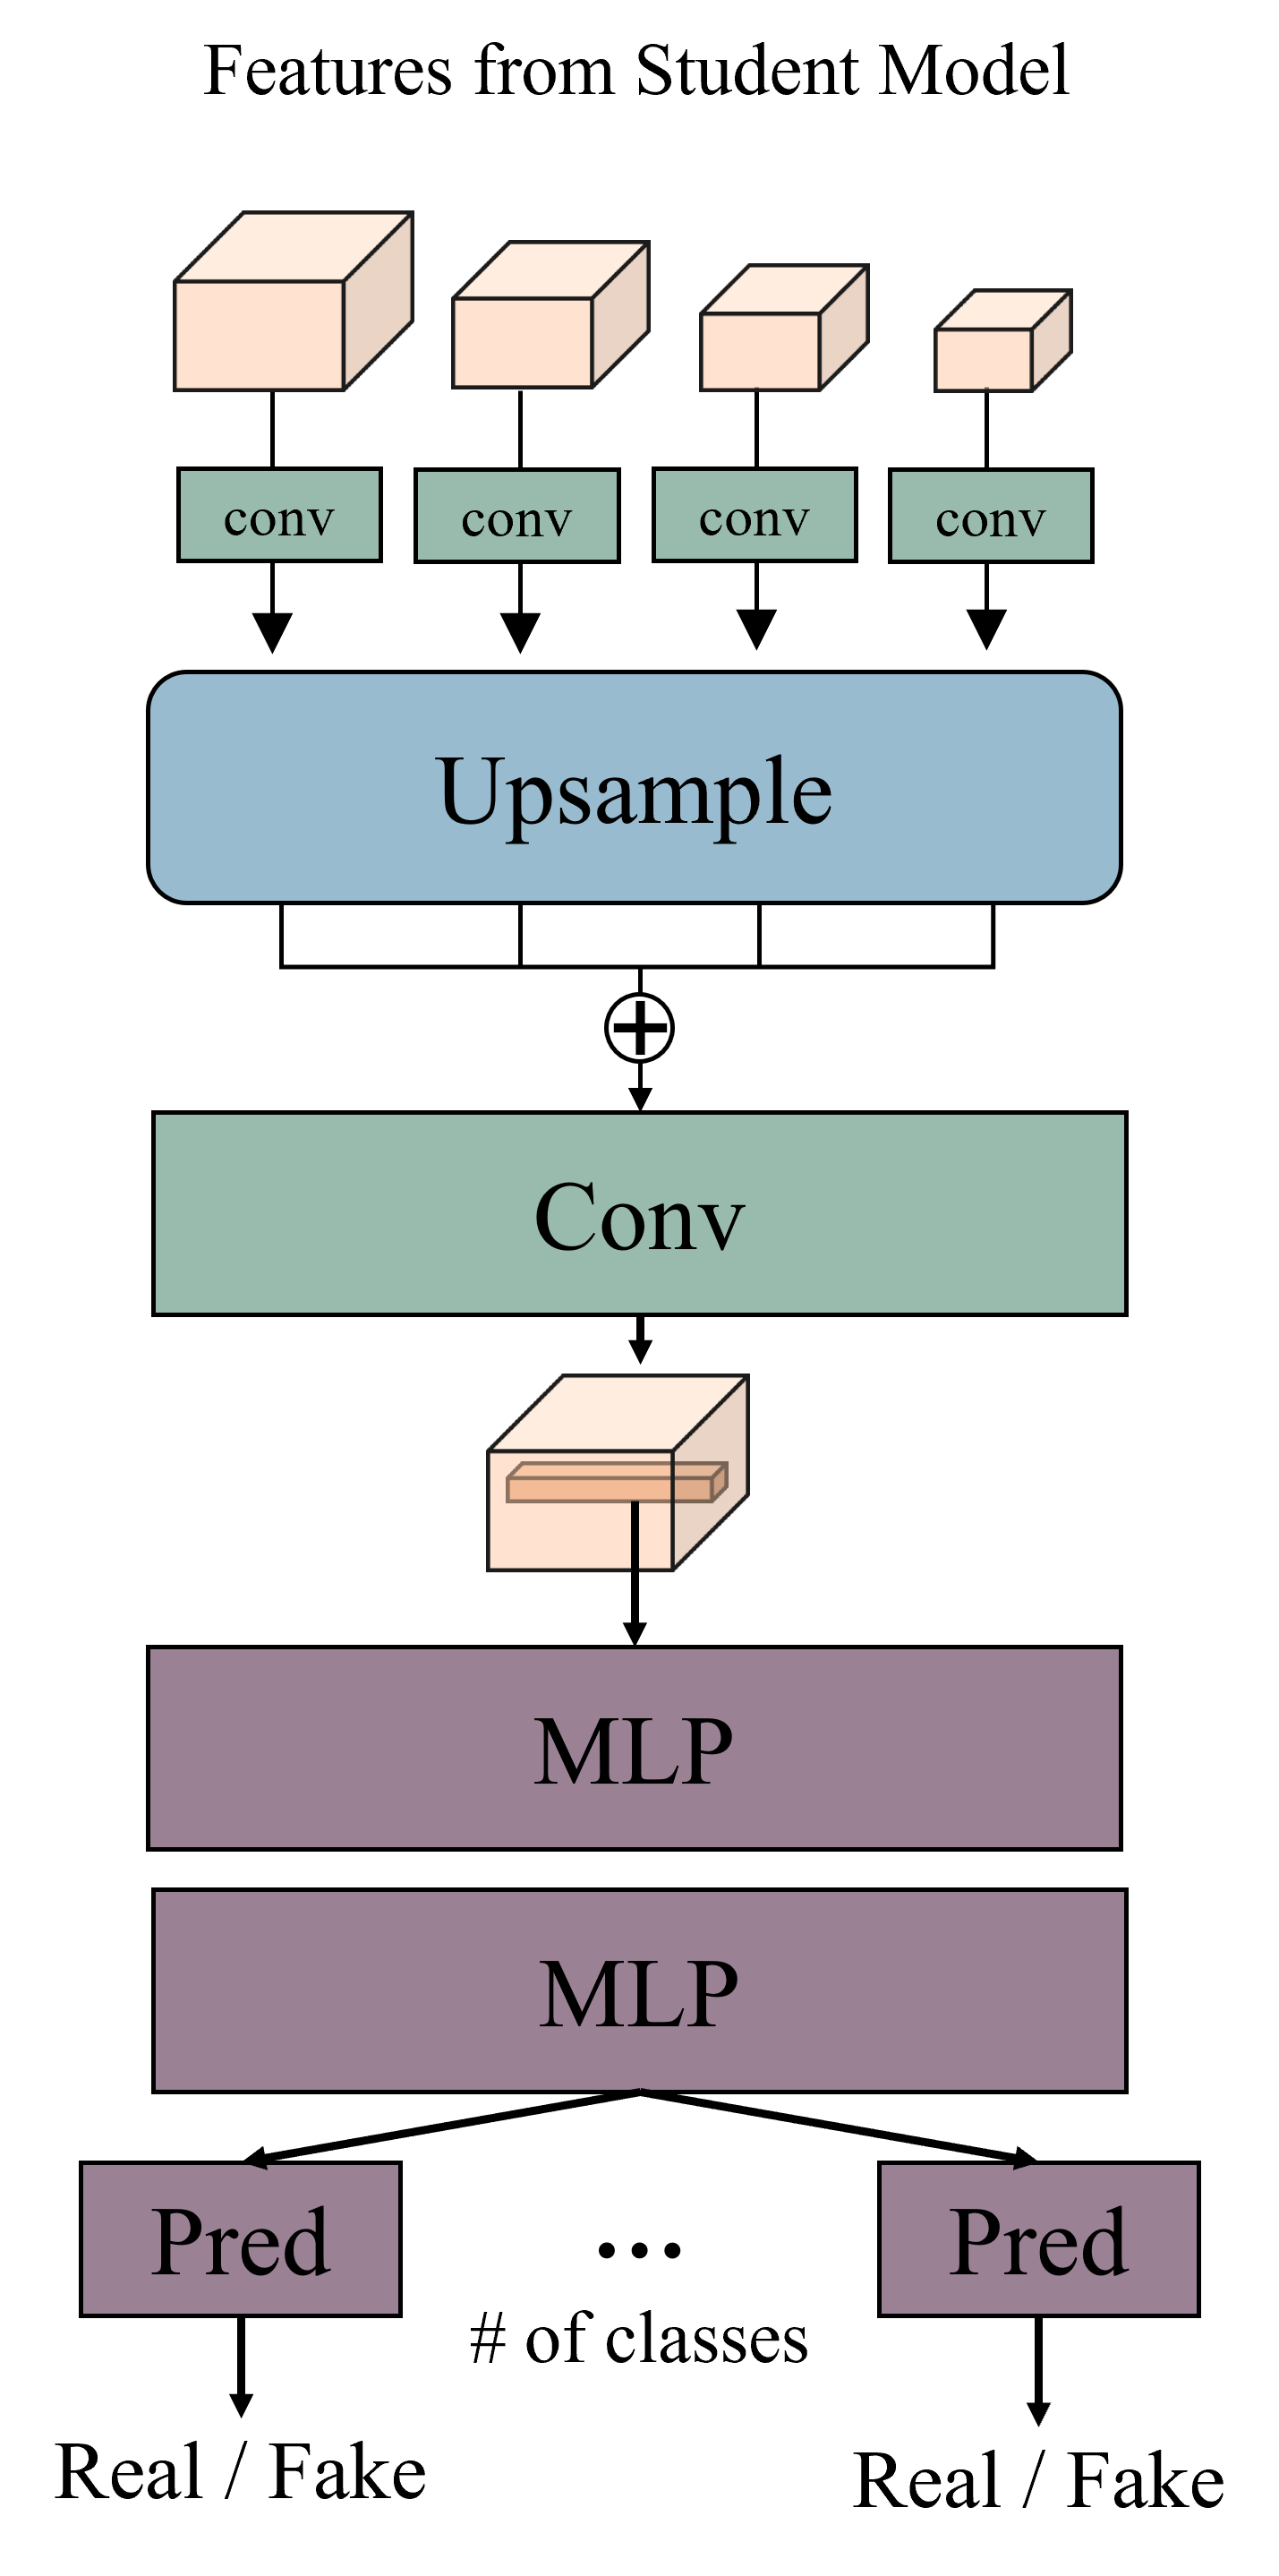

To resolve this problem, we propose a novel voxel-wise feature discriminator for embedding class-specific features of both labeled and unlabeled data. As presented in Fig. 3a, our voxel-wise feature discriminator takes a set of multiresolution features, , as an input, where denotes an encoder of the backbone, and denotes features from the hidden layer. These features from multiple hidden layers pass through the convolution layer to adjust the channel size, and each feature is upsampled to the same spatial size. Such features from multiple hidden layers are fused into one by adding an operation and a convolution layer. Thereafter, voxel-level features (-d vector) from this fused feature, , pass through a voxel-level feature discriminator, which consists of two multilayer perceptron networks (MLPs) and prediction layer (i.e., linear branch). The number of prediction layers corresponds to the number of class (in case of LA dataset, there exist two classes; foreground and background). The voxel-level features from different classes pass through different prediction layers. To specify the class of each voxel-level feature, we use ground-truth label for labeled data and pseudo-labels for unlabeled data, which can be computed using the following equation:

This different prediction branches enable multiple simultaneous adversarial classification tasks. We define features from labeled data as real and those from unlabeled data as fake so that the encoder of the segmentation network (generator) can generate voxel-level features of unlabeled data with a distribution similar to that of voxel-level features of labeled data. This forces the distributions of class-specific voxel-level features from both labeled and unlabeled features to be close. In this manner, the segmentation network can learn class-specific context-aware features more effectively. The encoder can embed both local and global features using a multiresolution context-fusion technique. In representing the voxel-wise feature discriminator, we can define our proposed adversarial loss function as follows: